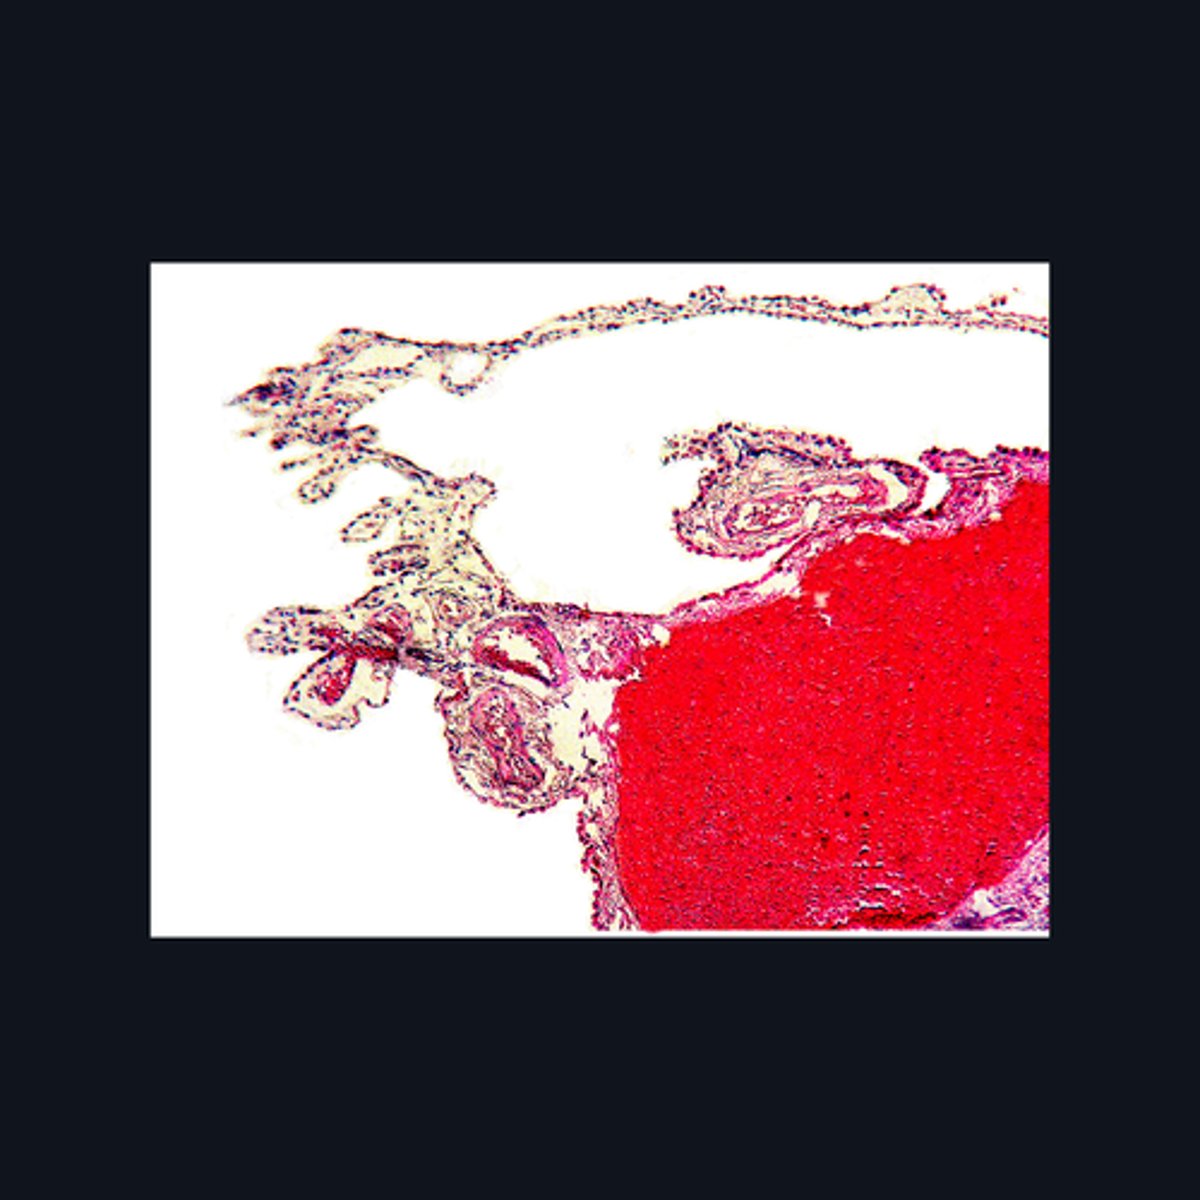

Meninges

What covers this structure of the brain?

Sulci

Outer surface of cerebral hemisphere is highly folded to form convolutions known as

Plexiform (Molecular) Layer, Outer Granular Layer, Pyramidal Cell Layer, Inner Granular Layer, Ganglionic Layer, Multiform Cell Layer

What are the six poorly-designed layers of this structure?

Folia

The surface of the cerebellum exhibits transverse folds called the _____.

Choroid Plexus

Identify the region of the brain in the given image.